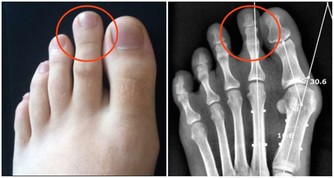

第6名:海鮮+啤酒

很多人喜歡就海鮮喝啤酒。

海鮮產品是高蛋白食物,含有嘌呤和苷酸成分,和啤酒混合在一起,會產生過多的尿酸和尿素氮等代謝物,

加重腎臟負擔,易導致高尿酸血症,甚至腎結石、尿毒症。